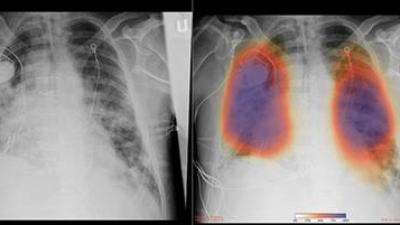

Pdf Deteccion Del Covid 19 Con Tecnicas De Deep Learning

www.researchgate.net

Deteccion De Covid 19 En Imagenes De Rayos X Con Keras Tensorflow Y Deep Learning By Datacampero Medium

medium.com

Se Desarrolla En Colombia Modelo De Inteligencia Artificial Para La Deteccion Complementaria Del Covid19 News Center Latinoamerica

news.microsoft.com